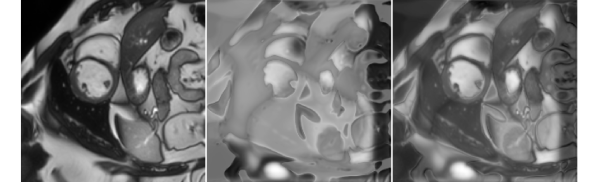

(a) image ()

(b) deformation field

(c) transformed

over image (v)

image ()

(i) Transformed images are obtained by applying deformation fields produced by Generator .

(ii) Transformed images are obtained by applying random elastic deformations.